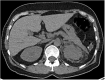

Erdheim-Chester disease (ECD) is a rare histiocytic disorder, recently recognized to be neoplastic. The clinical phenotype of the disease is extremely heterogeneous, and depends on the affected organs, with the most frequently reported manifestations being bone pain, diabetes insipidus and neurological disorders including ataxia. In this article, we report on a case of a 48-year-old woman, whose initial symptom of gait instability was isolated. This was associated with positional nystagmus with central features: nystagmus occurring without latency, clinically present with only mild symptoms, and resistant to repositioning maneuvers. The cerebral MRI showed bilateral intra-orbital retro-ocular mass lesions surrounding the optic nerves and T2 hyperintensities in the pons and middle cerebellar peduncles. A subsequent CT scan of the chest abdomen and pelvis found a left "hairy kidney", while 18 F-FDG PET-CT imaging disclosed symmetric 18F-FDG avidity predominant at the diametaphyseal half of both femurs. Percutaneous US-guided biopsy of perinephric infiltrates and the kidney showed infiltration by CD68(+), CD1a(-), Langerin(-), PS100(-) foamy histiocytes with BRAF V600E mutation. The combination of the different radiological abnormalities and the result of the biopsy confirmed the diagnosis of ECD. Many clinical and radiological descriptions are available in the literature, but few authors describe vestibulo-ocular abnormalities in patients with ECD. Here, we report on a case of ECD and provide a precise description of the instability related to central positional nystagmus, which led to the diagnosis of ECD.